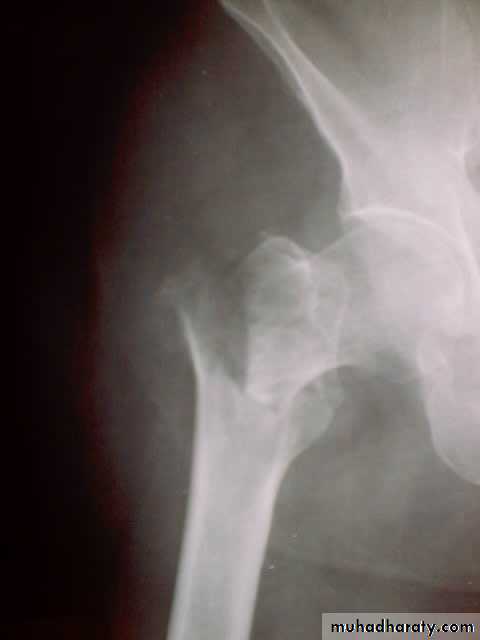

HIP DISLOCATION

Posterior dislocation:

Mechanism of injure:

4 out of 5 traumatic hip dislocations are posterior.

Usually occur in road traffic accident when the knee striking the dashboard

the femoral head is forced out of its socket sometimes associated with fracture.

Clinically:

O\E

Leg is short, internally rotated, adducted ,

and slightly flexed hip.

Radiological examinations

X-R AP view we can see the dislocation with or without associated fracture posterior wall of the acetabulum,

or fracture head of the femur,

And neck of femur.